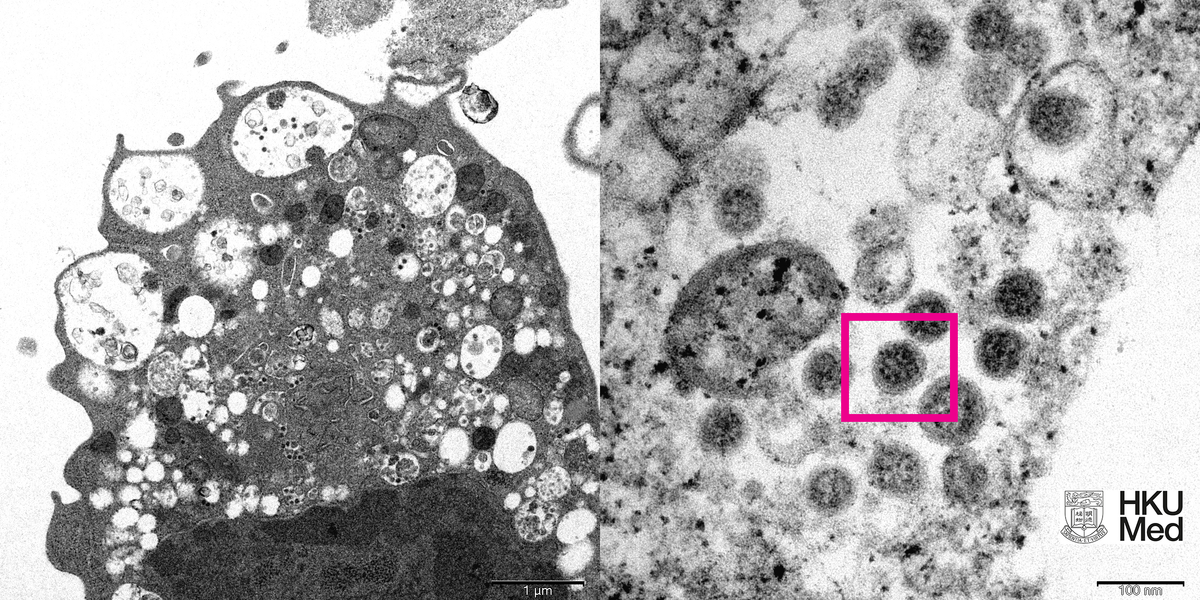

Hình ảnh biến thể Omicron của virus SARS-CoV-2.

Các nhà nghiên cứu giải thích, ở độ phóng đại thấp (bên trái), hình ảnh cho thấy tổn thương tế bào với các nang nước sưng lên chứa các hạt virus nhỏ màu đen. Ở độ phóng đại cao (bên phải), hình ảnh cho thấy tập hợp các hạt virus có gai hình hào quang (corona) trên tế bào.